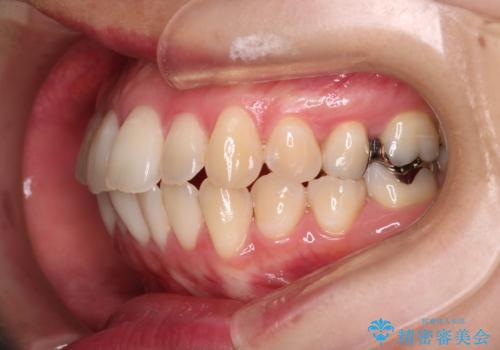

- 前歯のガタガタを主訴に来院された患者様です。

前歯の傾きも少し内側に入るように計画をたて、インビザラインにて治療を行いました。

このぐらいのガタガタであれば、インビザラインで簡単に治すことができます。